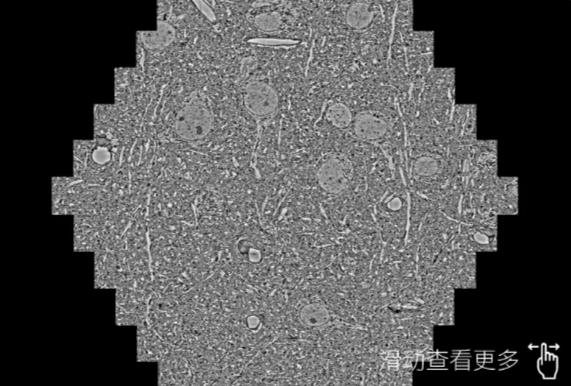

鼠脑切片。左图使用许昌蔡司许昌扫描电镜MultiSEM706对165μmx143pm面积区域成像,耗时仅需1.5秒。右图为鼠脑切片中30μm区域放大效果。样品由芝加哥大学B.Kasthuri提供。

使用蔡司高速许昌扫描电镜MultiSEM对1mm²人脑皮层组织进行高分辨成像,并对其中的各种细胞结构进行三维重构分析。左图展示了2x3mm²组织平面中锥体神经元的三维重构效果。右图显示了局部体积神经元三维重构。图像由哈佛大学chtman实验室提供,渲染图由D. Berger 制作。